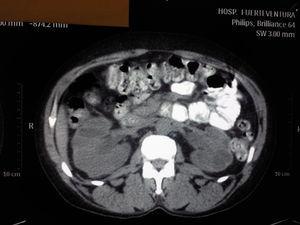

Presentamos el caso de una paciente mujer de 41 años de edad, sin antecedentes personales de interés que es remitida desde el servicio de urgencias por deterioro de función renal con creatinina sérica (Crs) 6.5 mg/dl, en el contexto de hemorragias vaginales con requerimientos transfusionales, siendo diagnosticada en ese momento por el servicio de ginecología de útero miomatoso. Se cursa ingreso para estudio, realizándose eco renal donde se objetiva una hidronefrosis bilateral grado IV con escasa diferenciación corticomedular sin objetivarse uréteres, por lo que se realiza tomografía axial computerizada (TAC) con el resultado de ureterohidronefrosis bilateral grado IV secundaria a compresión extrínseca por útero miomatoso de 13 x 9 cm (figura 1 y figura 2). Se avisa al servicio de urología, que implantan un catéter doble "J" en uréter derecho, con imposibilidad de colocación en uréter izquierdo. Se pide valoración por el servicio de ginecología, que postpone cirugía de histerectomía simple para una semana después. Tras realización de histerectomía, la paciente evoluciona desde el punto de vista clínico de forma favorable, no así desde el punto de vista bioquímico, manteniéndose Crs de 4.5 mg/dl tras 15 días postoperatorio. Se realizó nueva ecografía renal observándose hidronefrosis grado II y escasa diferenciación corticomedular, por lo que no se realizó biopsia renal percutánea, decidiéndose alta a domicilio con el diagnóstico de enfermedad renal crónica grado 4 secundaria a probable nefritis intersticial, para seguimiento en consulta de prediálisis.

Figura 2.